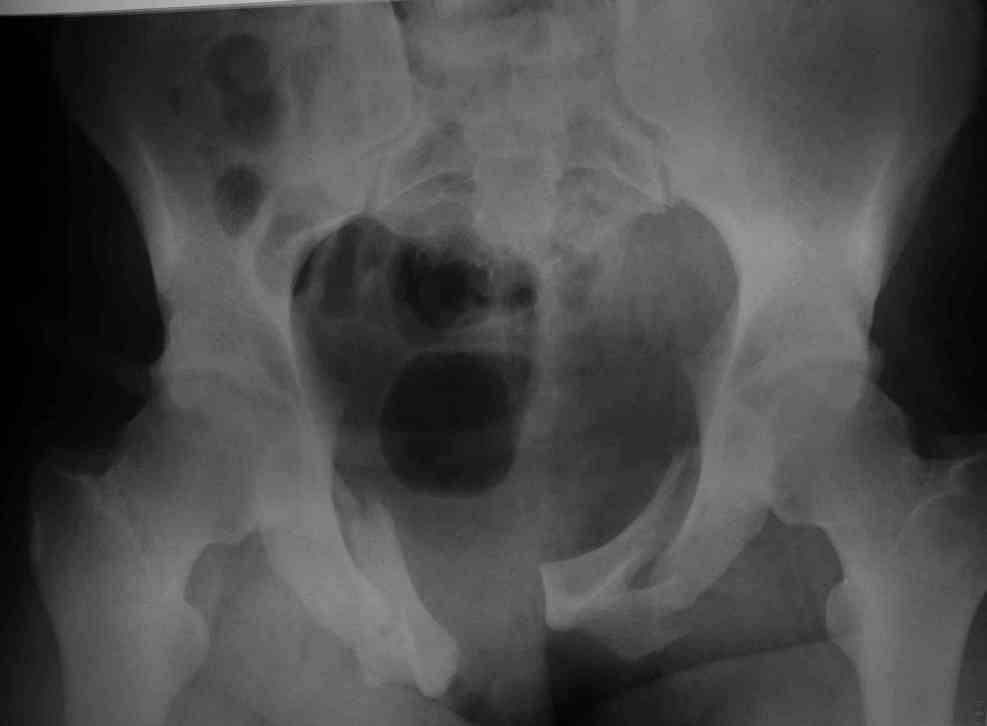

Уважаемые коллеги! опять вопрос по повреждению таза. Больной получил производственную травму 10 дней назад - удар балкой около 3 тонн в область верхней трети правого бедра и лона.

Был диагностирован перелом "типа бабочки" и повреждение уретры. Сделана цистостома. У насв отделении 3 дня. Имеется огромная флюктуирующая гематома с "галифе"-образной деформацией обеих бедер. Пнкционно эвакуировали в несколько приемов из подфасциальных полостей на бедрах около 3 литров геморрагического отделяемого с последующей эластической компрессией. При пункциях выявлено сообщение полостей на бедрах - видимо через поравннуюдиафрагму дна и полость таза - при удалении крови справа уменьшался объем левого бедра. Какой то активности проявялять покабоимся - аппаратная фиксация через отслоенные ткани представляется чреватой нагноением, открытая фиксация в условиях такой гематомы тоже не радует. Хотелось бы услышать ваше мнение

18.12. - отдельное спасибо еще раз А.В.Рункову- больного оперировали (А.В.Рунков) - произведен остеосинтез аппаратом - фиксация за крылья, два стержня в лонные кости и репозиция (почти полная) снимки будут чуть позже.

Дренировали отслойки на бедрах с их санацией. В правой ягодичной области сформировалась зона некроза. Больной "подвешен" за аппарат.